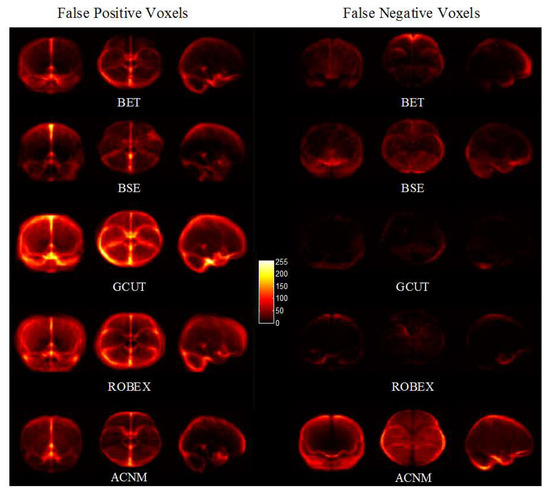

4. Discussion